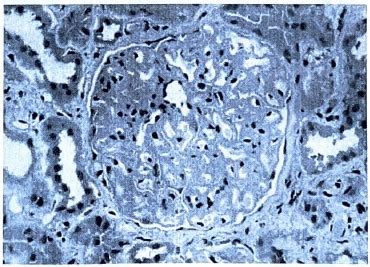

Pathophysiology of Pulmonary Tuberculosis

Pathology of Tuberculosis

Pathophysiology of TB

Pathogenesis of Tuberculosis

Pathophysiology Diagram of TB